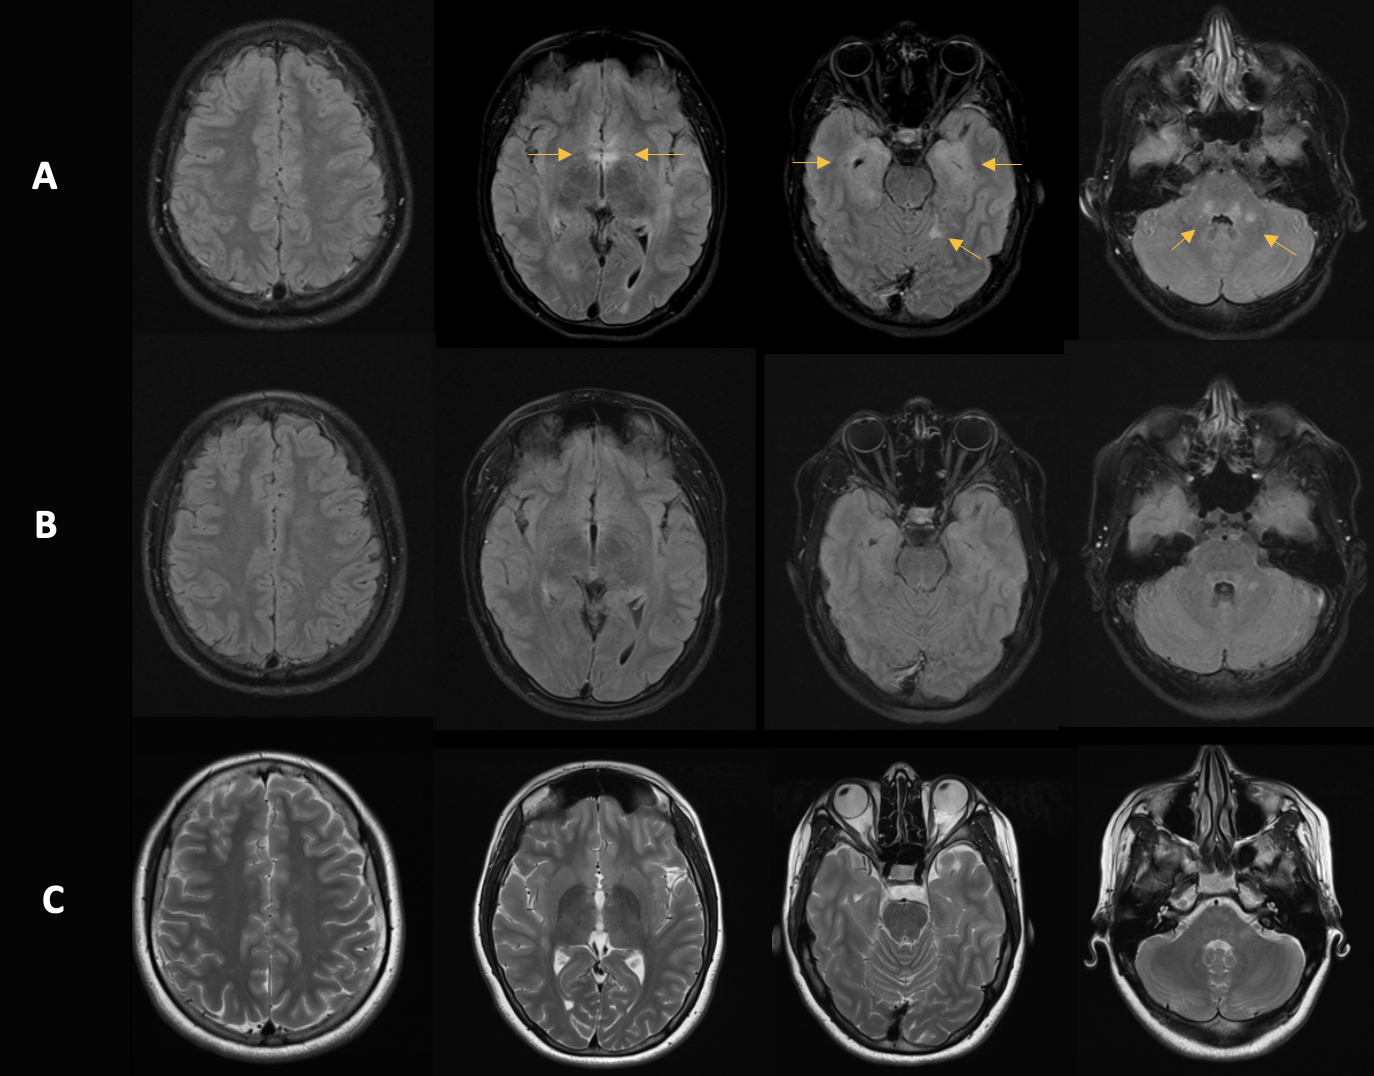

Bildgebung:

Mittels notfallmäßiger Computertomographie wurde eine Akutpathologie wie Blutung oder Infarkt ausgeschlossen. Anschließend wurde eine Magnetresonanztomographie durchgeführt, diese zeigte die folgenden pathologischen Veränderungen (siehe folgende Abbildung 1):

MRT-Befund:

Die MRT-Untersuchung zeigte ausgeprägte T2w-Hyperintensitäten in der Medulla oblongata, weniger im kaudalen Tegmentum pontis, im zerebellären Marklager rechts, im subkortikalen Marklager am Hinterhorn links, insulär/temporal rechts, um die Temporalhörner, im posterioren Cingulum rechts und frontal beidseits. Der bildgebende Befund ist vereinbar mit einer limbischen Enzephalitis.